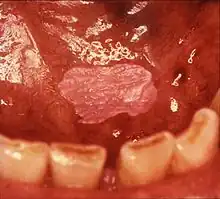

Non-homogeneous leukoplakia is a lesion of non-uniform appearance. The color may be predominantly white or a mixed white and red. The surface texture is irregular compared to homogeneous leukoplakia, and may be flat (papular), nodular or exophytic.[9][15] "Verrucous leukoplakia" (or "verruciform leukoplakia") is a descriptive term used for thick, white, papillary lesions. Verrucous leukoplakias are usually heavily keratinized and are often seen in elderly people. Some verrucous leukoplakias may have an exophytic growth pattern,[2] and some may slowly invade surrounding mucosa, when the term proliferative verrucous leukoplakia may be used. Non-homogeneous leukoplakias have a greater risk of cancerous changes than homogeneous leukoplakias.[9]

Erythroleukoplakia (also termed speckled leukoplakia, erythroleukoplasia or leukoerythroplasia) is a non-homogeneous lesion of mixed white (keratotic) and red (atrophic) color. Erythroplakia (erythroplasia) is an entirely red patch that cannot be attributed to any other cause. Erythroleukoplakia can therefore be considered a variant of either leukoplakia or erythroplakia since its appearance is midway between.[22] Erythroleukoplakia frequently occurs on the buccal mucosa in the commissural area (just inside the cheek at the corners of the mouth) as a mixed lesion of white nodular patches on an erythematous background,[22] although any part of the mouth may be affected. Erythroleukoplakia and erythroplakia have a higher risk of cancerous changes than homogeneous leukoplakia.[22]

- Red lesions (erythroplasia) and mixed red and white lesions (erythroleukoplakia/"speckled leukoplakia") have a higher risk of malignant change than homogeneous leukoplakia.[15]